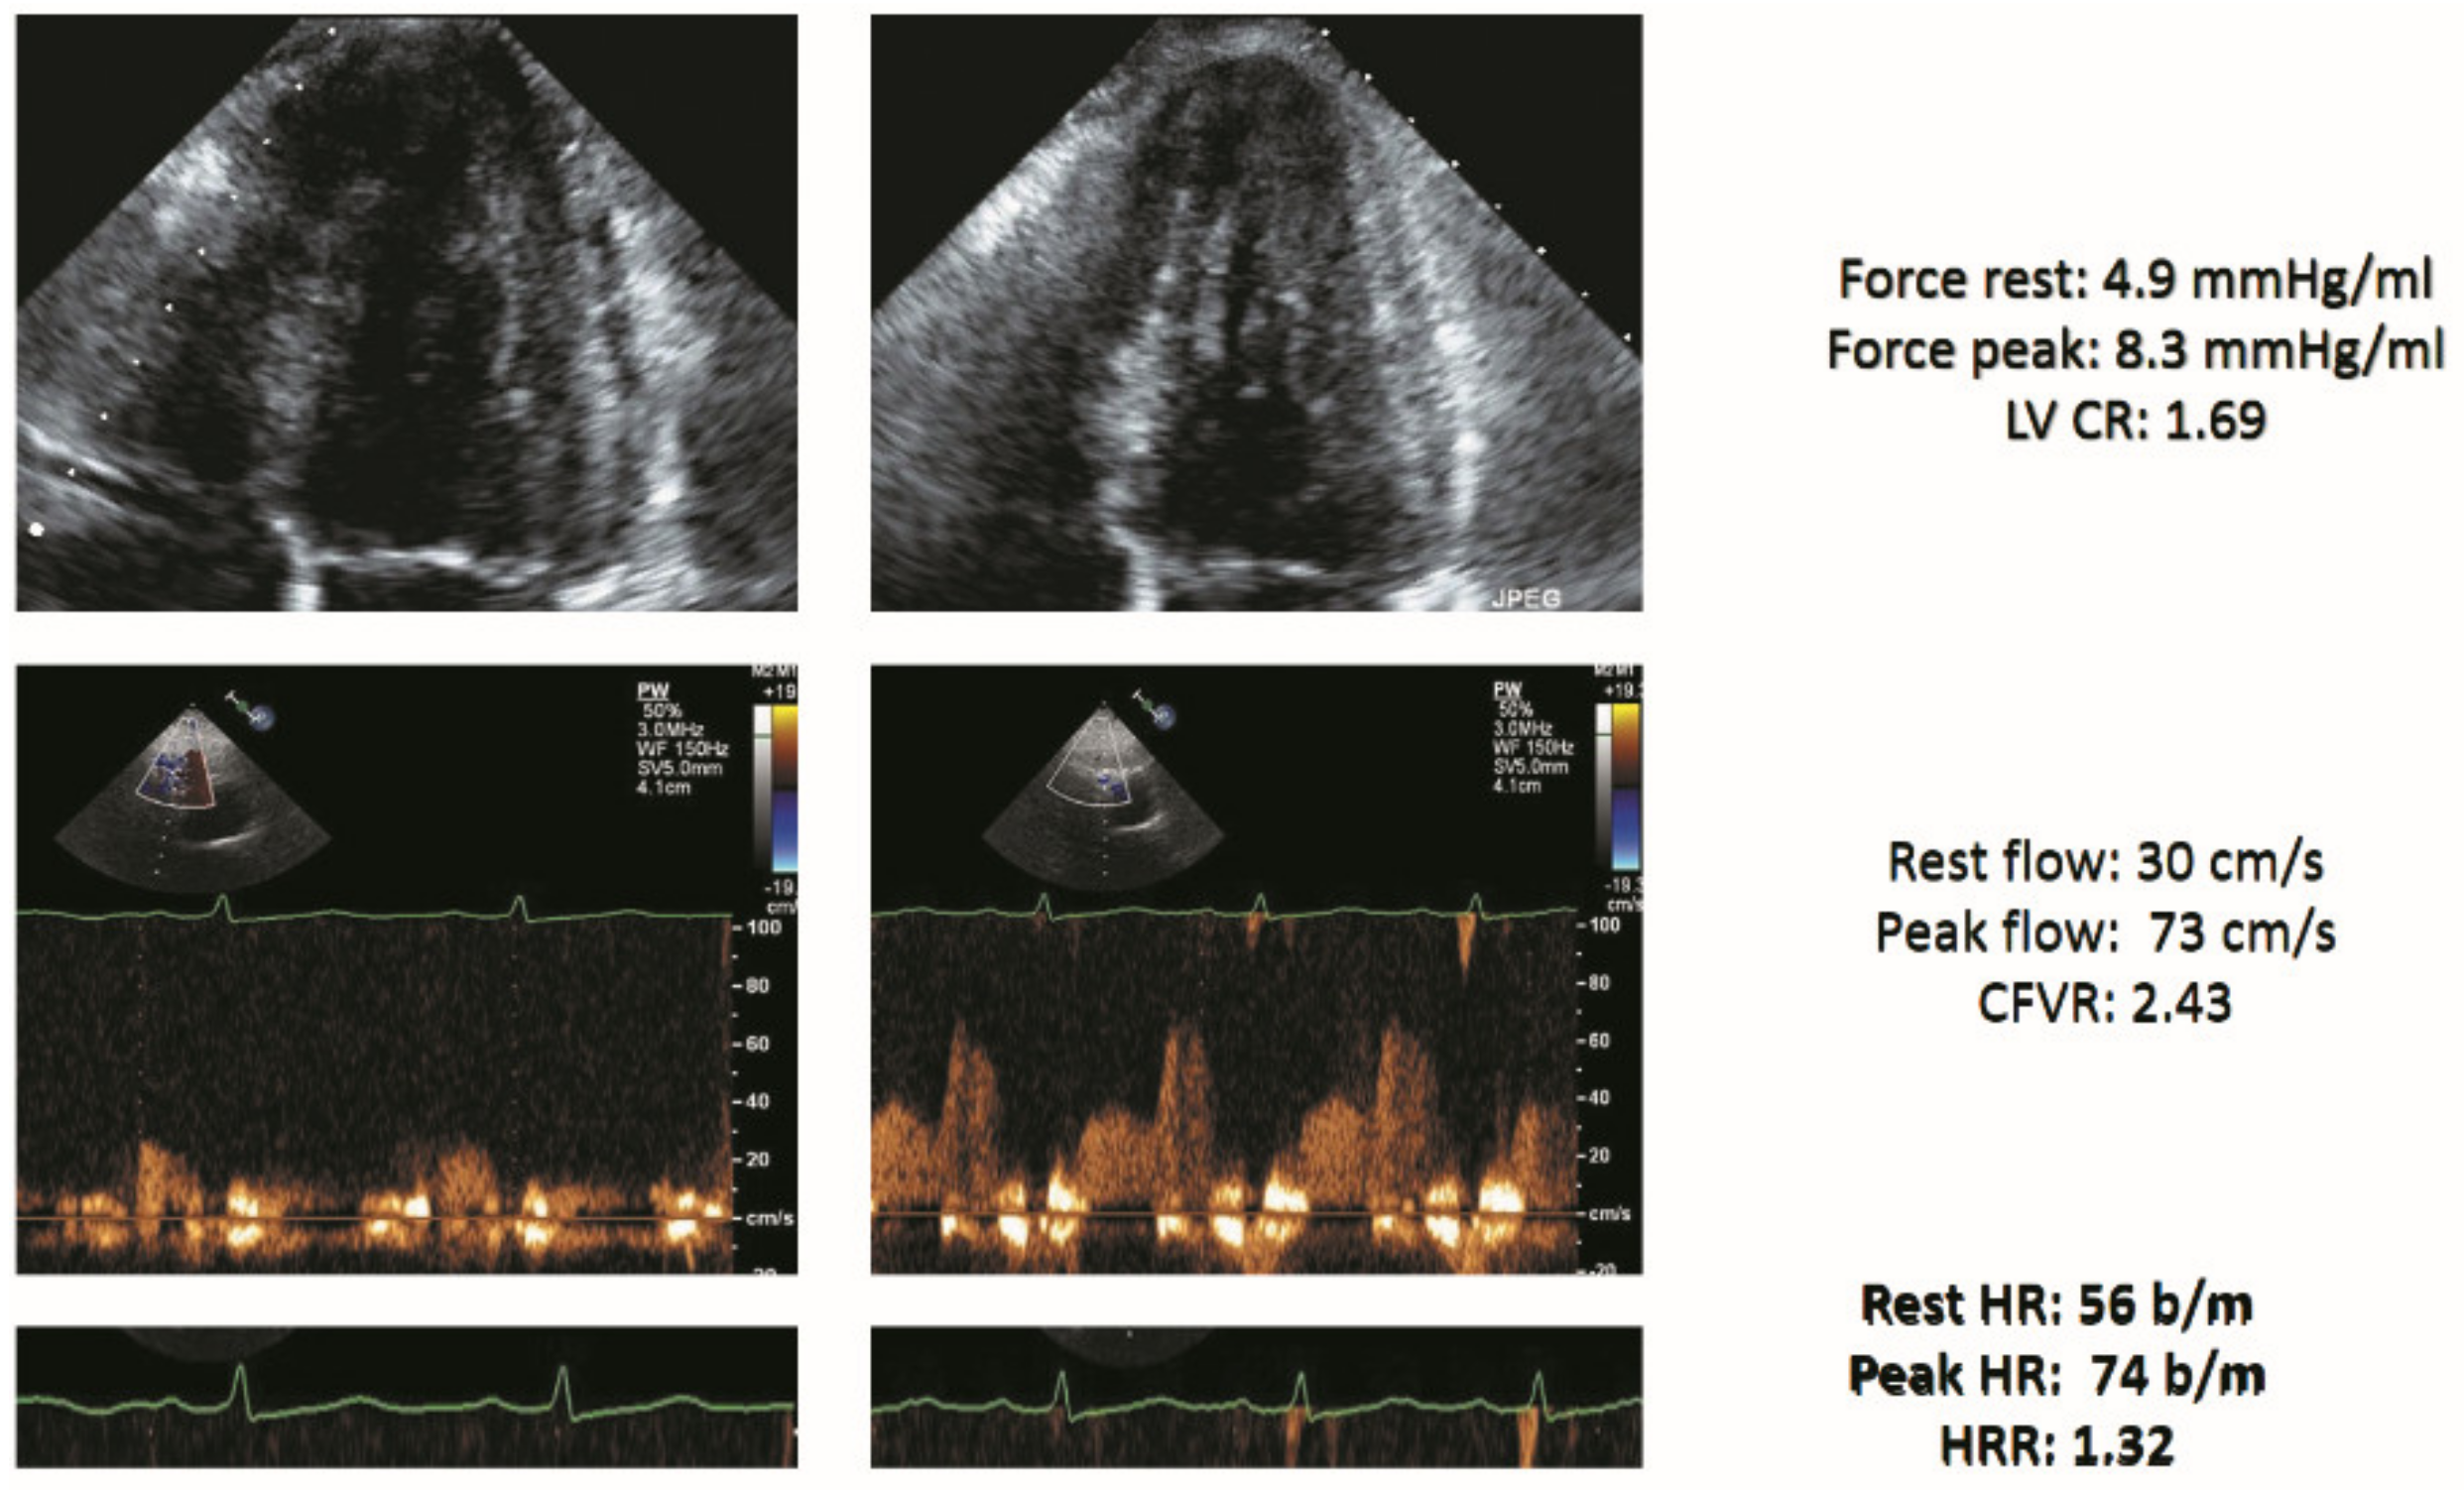

| Rest force (mmHg/mL) | 3.0 ± 2.0 | 4.7 ± 1.7 | 4.4 ± 1.1 | 1.1 ± 0.5 | <0.001 |

| Stress force (mmHg/mL) | 4.0 ± 3.3 | 6.6 ± 3.1 | 3.0 ± 1.8 | 1.2 ± 1.1 | <0.001 |

| LV CR | 1.24 ± 0.38 | 1.41 ± 0.39 | 1.20 ± 0.25 | 1.02 ± 0.33 | <0.001 |

| Rest CFV (cm/s) | 29.6 ± 8.4 | 27.6 ± 8.5 | 31.0 ± 7.7 | 31.4 ± 8.3 | <0.001 |

| Stress CFV(cm/s) | 65.5 ± 22.6 | 64.3 ± 16.9 | 68.2 ± 15.9 | 65.1 ± 22.6 | 0.108 |

| CFVR | 2.24 ± 0.47 | 2.38 ± 0.39 | 2.24 ± 0.42 | 2.06 ± 0.54 | <0.001 |

| Rest HR (bpm) | 70.7 ± 11.3 | 69.5 ± 10.6 | 69.3 ± 10.8 | 73.3 ± 12.2 | <0.001 |

| Peak HR (bpm) | 88.6 ± 15.0 | 90.4 ± 16.1 | 86.9 ± 13.6 | 87.5 ± 14.1 | 0.030 |

| HRR | 1.26 ± 0.17 | 1.31 ± 0.18 | 1.26 ± 0.16 | 1.20 ± 0.16 | <0.001 |